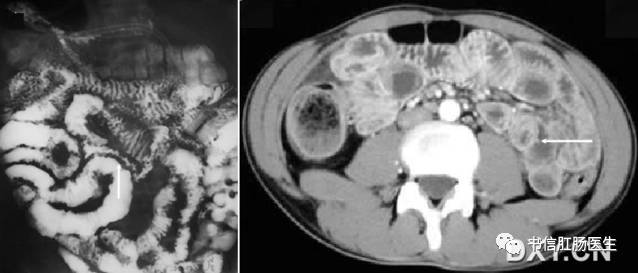

1. 胃肠细绳征(胃肠线征、绳征、绞索现象)

★ 左图:克罗恩病 X 线小肠钡剂灌肠,病变肠腔不规则狭窄(白色箭头),段壁僵硬,呈节段性分布;右图:CT 横断面示小肠肠壁节段性增厚,肠腔狭窄(白色箭头)。

■ 影像表现:在小肠钡剂检查中,小肠形成类似于粗糙棉线一样的细钡线。

■ 征象解析:胃肠道严重狭窄,导致内腔呈线样改变,胃肠细绳征经常作为内腔狭窄的一个术语,最初用于描述克罗恩病的可逆性狭窄。狭窄原因是由于严重溃疡引起易激和痉挛所致的不完全性梗阻,且可以发现狭窄与扩张交替。当狭窄主要由水肿和痉挛引起时,狭窄程度不是一致的,如小肠壁因纤维化而增厚,则肠腔的内径表现为一致变窄。黏膜被纤维坏死组织所替代,偶尔黏膜岛仍可被发现。

■ 讨论:胃肠细绳征己被证实为克罗恩病的特征性表现,最常出现在末段回肠。早期克罗恩病的肠道异常包括粗绒毛征、皱襞增厚和阿弗他溃疡。沿着肠系膜缘的线样溃疡是小肠克罗恩病最重要的影像特征之一,溃疡平行于短缩的、凹入的或者僵直的肠系膜缘。相邻的肠系膜增厚和回缩,特别在有受侵肠段的连接处。胃肠细绳征的出现高度提示克罗恩病,但它也可在其他疾病中出现。